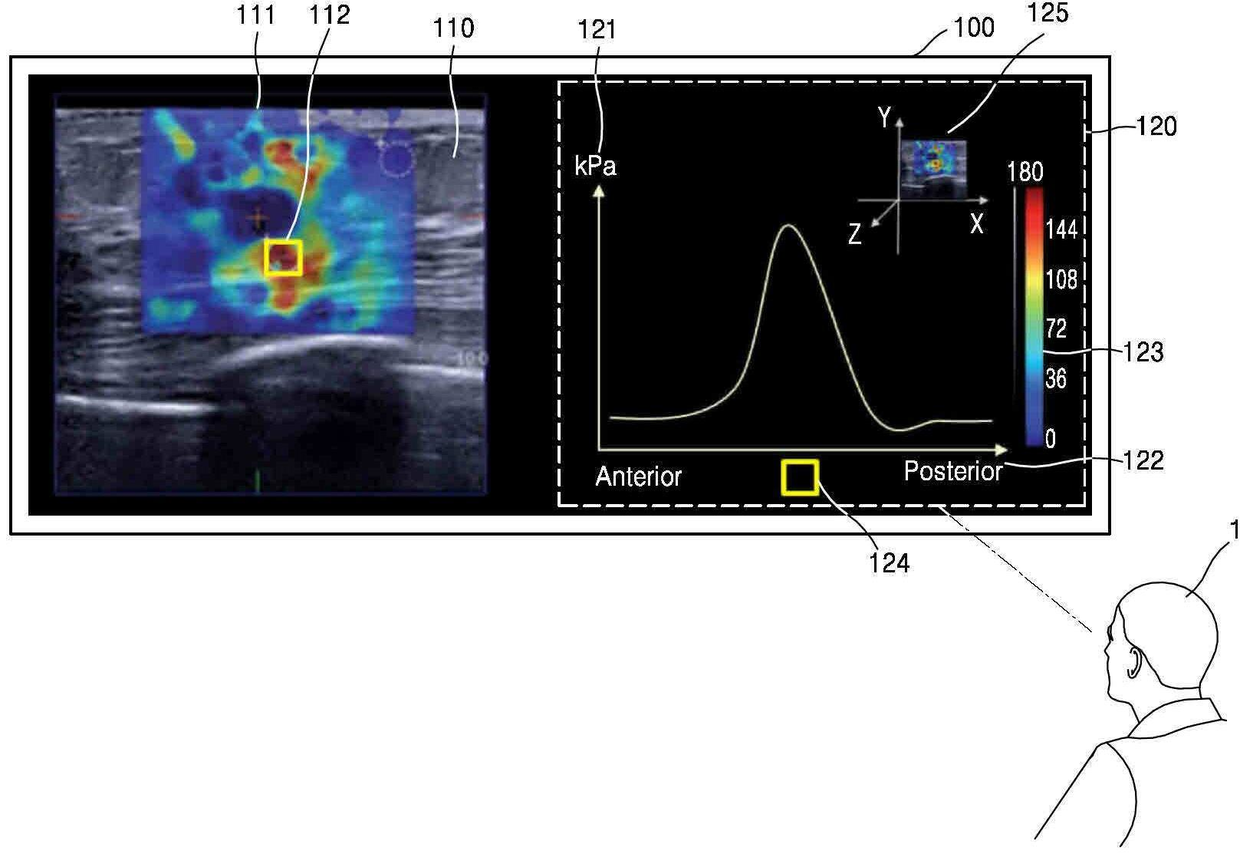

대상체에 관한 횡파 탄성 데이터를 표시하는 초음파 진단 장치 그 동작 방법